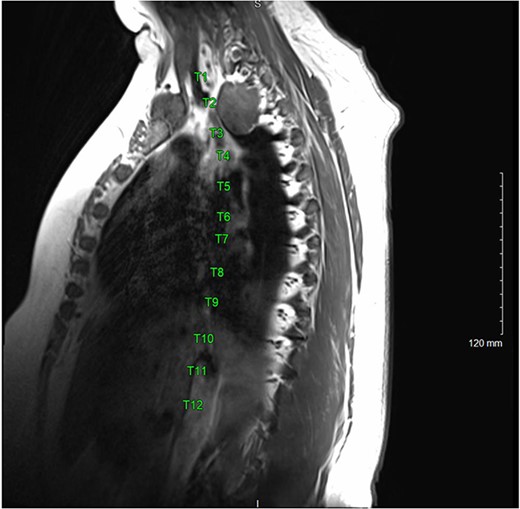

A magnetic resonance imaging (MRI) showed that the tumor extended into the outer aspect of the right T2-T3 neural foramen and could represent a nerve sheath tumor. Sixteen months later, neurosurgical consultation repeated her MRI, which showed that the mass had grown 2 mm (Figs 3 and 4). There was no extension into the neural foramen or bone erosion.